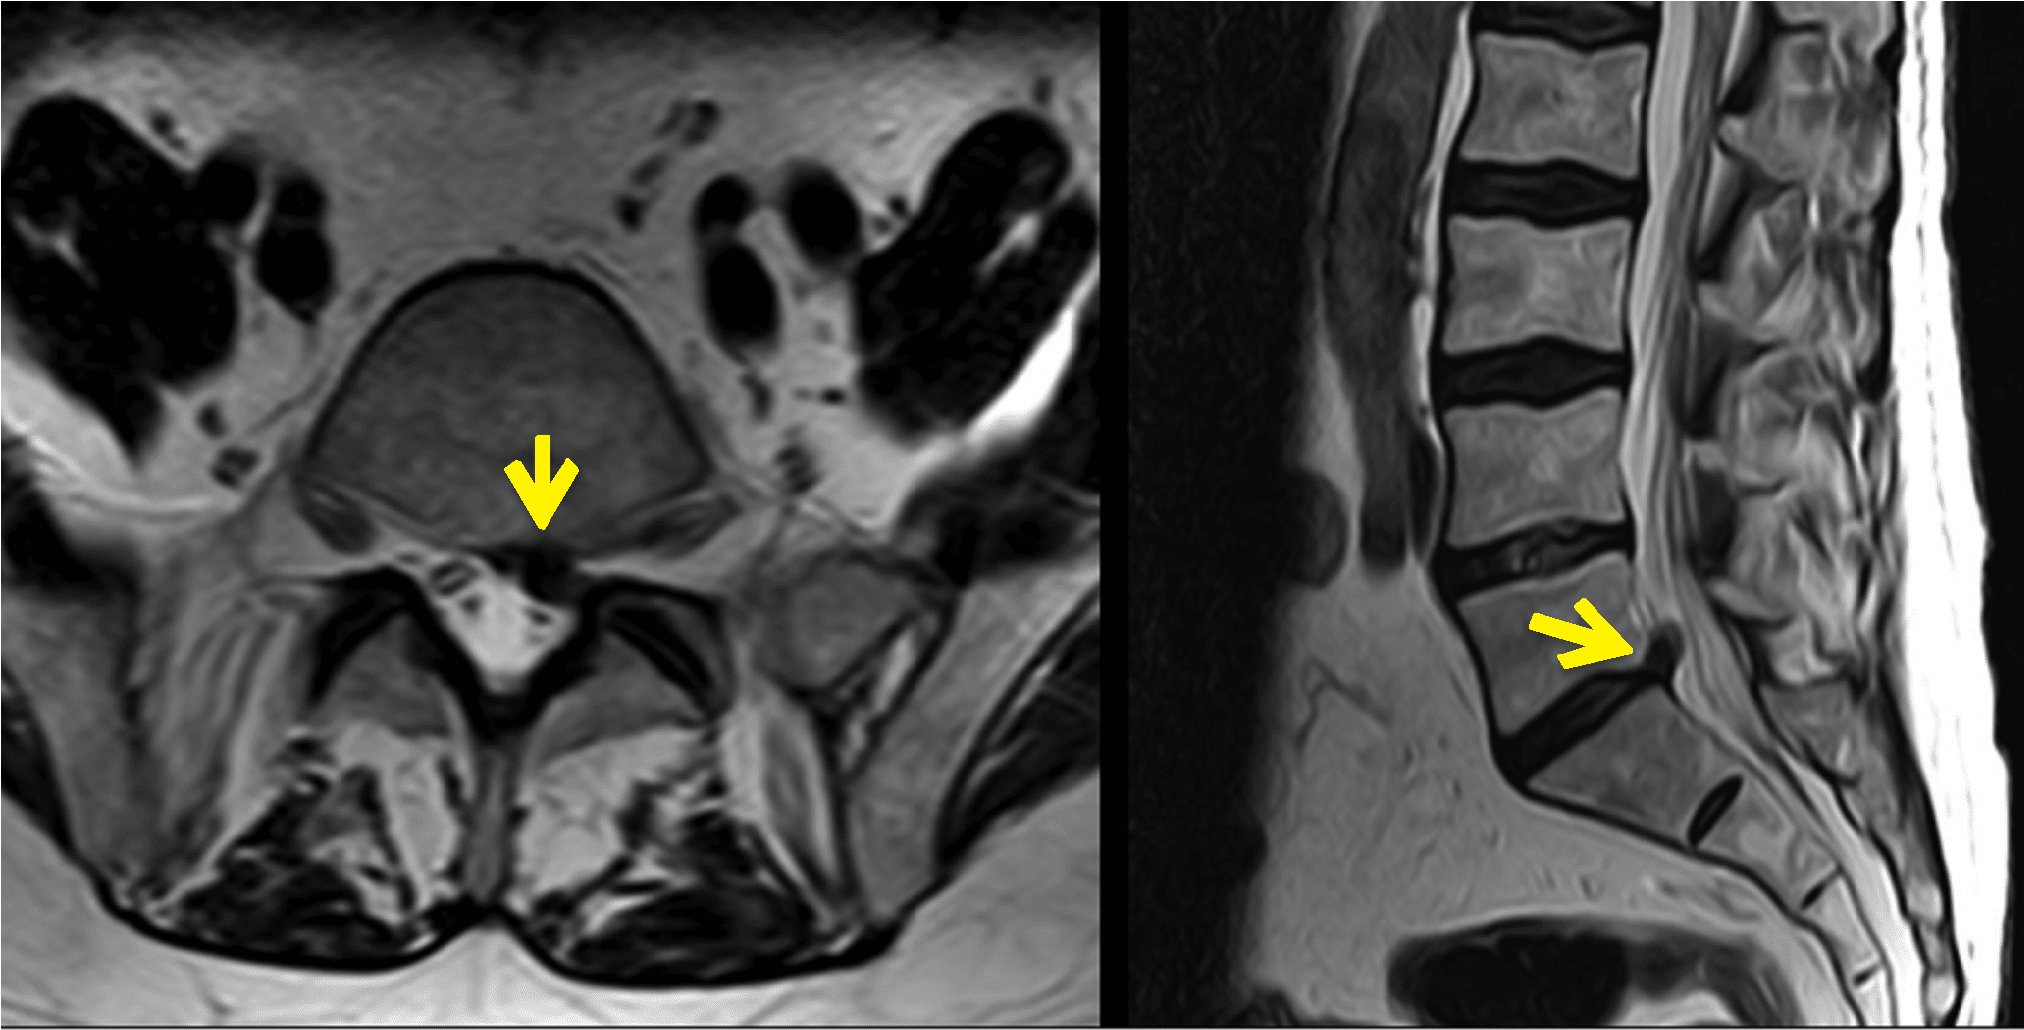

Thecal sac indentation occurs when there is pressure exerted on the thecal sac, causing it to compress or deform. This can happen due to various reasons, such as herniated discs, spinal stenosis, or other conditions that result in the narrowing of the spinal canal.

One common cause of thecal sac indentation is a herniated disc. When the soft inner core of a disc protrudes through the tough outer layer, it can press against the thecal sac, leading to indentation. Another cause is spinal stenosis, which is the narrowing of the spinal canal. This narrowing can put pressure on the thecal sac, causing it to indent.

If you suspect you have thecal sac indentation, it is essential to consult a healthcare professional for a proper diagnosis. Your doctor may recommend imaging tests such as MRI or CT scans to assess the extent of the indentation.

Thecal sac indentation is typically diagnosed through imaging tests like MRI or CT scans. These imaging studies can provide detailed pictures of the spinal structures, allowing healthcare professionals to identify any compression or indentation of the thecal sac.